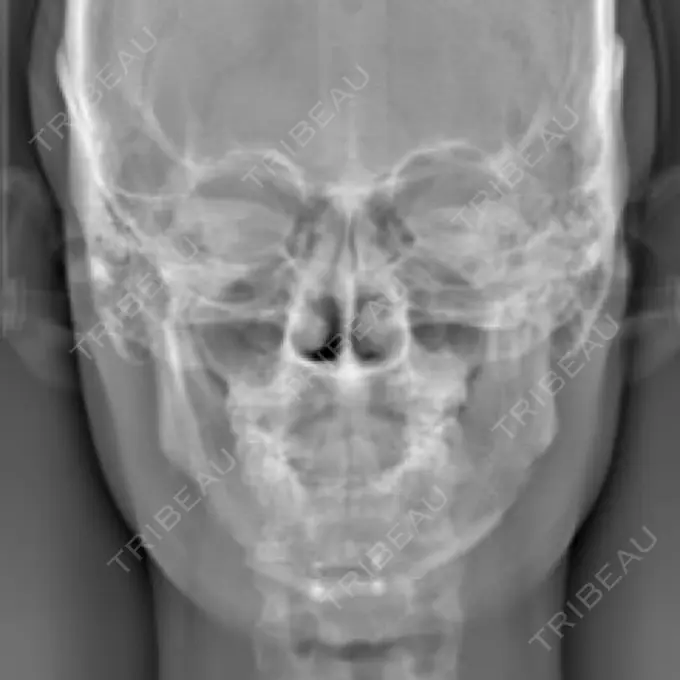

元々、左右差が酷かったので右側をオトガイ神経ギリギリまで切っていただき左はエラ部を中心に切りCTでも左右差が解消されていました。